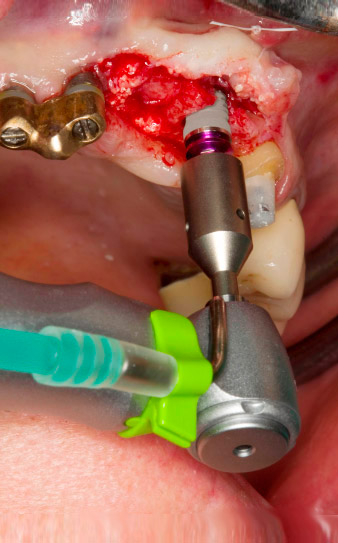

Following primary healing, the soft tissues were shaped using the basally lined bridge. Two months later the site was exposed by a slightly palatal alveolar ridge incision (Fig 2). The dimensions of the alveolar bone proved to be sufficient at position 22. Figures 2 and 4 show the preparation of the implant bed, the tapping and the implantation using Implantmed.

The new implantology motor was used with the appropriate W&H surgical contra-angle handpieces.

The preparation of the implant bed, tapping and implantation were performed with the new Implantmed implantology motor, which the author refers to as a thoroughly successful design. The manufacturer has really developed a whole range of technical features further in this device. For example, the sophisticated menu navigation system via the touch screen is particularly helpful. It is easy to select all the functions and they can be conveniently adjusted to the specific implant system and your personal preferences. This also applies for up to six users in a larger practice or a hospital.